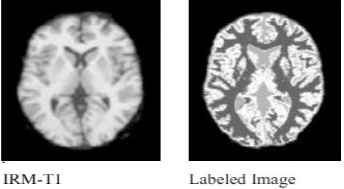

4.6. Final segmentation

A labeled image, created by assigning each voxel to the tissue class, for which it had the greatest membership. An example of both reference and computed segmented images are presented in Fig. 3. Nothing that the ground truth information is available from the synthetic and real databases.

Example of labeled image of a real IRM-T1 image slice. Tissues are labeled WM (dark gray color), GM (white color), and CSF (gray color).